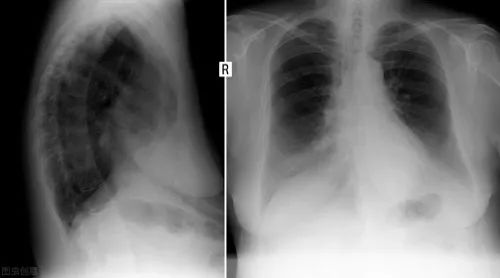

➍ 在发病 6 个月后,住院时病情更重的患者更可能呈现肺功能下降和胸部影像学异常。

图片来源:参考文献